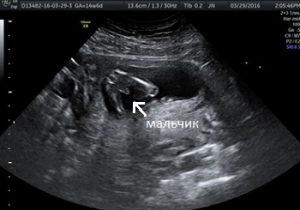

Большинство беременных женщин узнаёт пол своего ребёнка во время ультразвукового обследования (УЗИ). Обычно это происходит в середине беременности между 16-й и 20-й неделями, но некоторые современные методы иногда позволяют сделать это еще раньше – примерно после 10-й недели.

1. Традиционное ультразвуковое исследование

Определение пола будущего ребенка — тема, вызывающая много обсуждений и интереса. Многие родители начинают задаваться этим вопросом уже на ранних сроках беременности. Существуют различные методы, позволяющие узнать пол малыша. Наиболее распространенный способ — ультразвуковое исследование, которое обычно проводят на 18-20 неделе. Однако некоторые родители предпочитают дождаться рождения, чтобы сохранить элемент сюрприза.

Имейте в виду, что даже УЗИ не является на 100% точным, и были случаи, когда люди покупали одежду для мальчиков, а потом оказывалось, что у них девочка и наоборот.